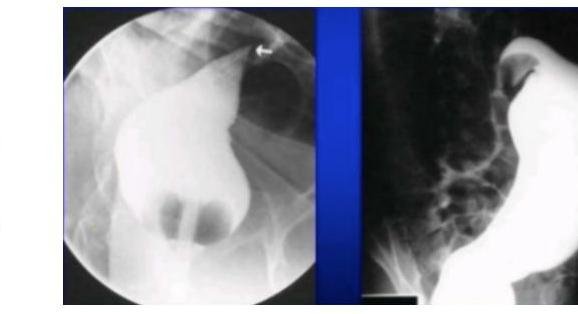

Contenido mejorado por IA (Markdown)

# VÓLVULO DE COLON ## DEFINICIÓN Un **vólvulo** se define como la torsión de un órgano a través de un eje, sobre su pedículo vascular. El vólvulo de colon típicamente resulta en una obstrucción intestinal en asa cerrada. La rotación del pedículo vascular y la dilatación del colon contribuye a compromiso de la perfusión del colon.  ## LOCALIZACIÓN 1. **SIGMOIDES** (la más frecuente) 2. Ciego (frecuente en mujeres de edad media)  # EPIDEMIOLOGÍA - Corresponde a 1 - 7 % de todas las oclusiones intestinales - Tasa de mortalidad 7 - 20 % - Es más común en América Latina, África y Europa del Este - En naciones de primer mundo es relativamente raro. - En esos países es la 3a causa de obstrucción de colon (después de neoplasias y enfermedad diverticular) ## FACTORES DE RIESGO CIEGO - Femeninos de edad media. - Cirugías abdominales previas - Adultos mayores con inactividad prolongada ## FACTORES DE RIESGO SIGMOIDES - Masculinos - Edad mayor 60 años - Pacientes adultos mayores institucionalizados - Estreñimiento crónico - Enfermedad neuropsiquiátrica - Retraso mental - Desórdenes neurológicos - Cirugías abdominales previas - Embarazo (**causa más frecuente de obstrucción**) - Infestación por gusanos redondos - Megacolon (Chagas y Hirschprung) ## CLINICA ## CUADRO DE OBSTRUCCIÓN INTESTINAL QUE CURSA CON DOLOR ABDOMINAL Y DISTENSIÓN (ASA CERRADA) ## - DOLOR ABDOMINAL - Distensión abdominal **SÚBITA Y ESPECTACULAR**. - Ausencia de canalización de gases - Ausencia de evacuaciones - Náusea y vómito - Hipersensibilidad abdominal - Resistencia muscular - Ruidos peristálticos de tono metálico - Fosa ilíaca izquierda vacía a la palpación abdominal **ISQUEMIA / PERFORACIÓN** Dolor Intenso + Irritación Peritoneal + Datos de Sepsis. - Ausencia de materia fecal en exploración rectal - Materia fecal melénica en el recto (poco común) # DIAGNÓSTICO Laboratorio: realizar BH, QS, ES y pruebas de coagulación en todos los sospechosos de Vólvulo. ## ESTUDIOS DE IMAGEN. ## RADIOGRAFÍA ABDOMEN - Permite diagnóstico en mayor porcentaje en los Sigmoides que en los Cecales - Solicitar de pie (buscando aire libre subdiafragmático = Perforación) y decúbito. - Realizarla en ausencia de TAC de urgencias ## Hallazgos Cecales: 1. Asa desproporcionadamente dilata y patrón de oclusión distal (91%) 2. Nivel hidroaéreo único en el ciego y colapso de colon distal (82%)  ## ENEMA DE BARIO - Es más útil en el sigmoides que en el cecal - Contraindicada en sospecha de peritonitis. - Realizarlo en sospecha de Vólvulo sigmoides cuya radiografía no sea concluyente o TAC no accesible. - Imagen en "pico de ave" o "as de espadas" en el punto del vólvulo sigmoides, producida por el medio de contraste en el enema de bario.  ## TOMOGRAFÍA COMPUTARIZADA Es el **ESTUDIO CON MAYOR PROBABILIDAD DIAGNÓSTICA** tanto en Sigmoides (89%) y Ciego (71.4%). ## Hallazgos Sigmoides - Signo del Grano de café + Nivel hidroaéreo único + Colapso de Colon Izquierdo - Signo del remolino (flecha roja) - - Distensión del ciego de +10 cm  # TRATAMIENTO SIGMOIDES ## MANEJO MÉDICO 1. REANIMACIÓN TEMPRANA: - Balance adecuado de líquidos y electrolitos - Apoyo ventilatorio (en caso necesario) - Descompresión Intestinal con **SONDA NASOGÁSTRICA** 2. ANTIBIÓTICOS: deben ser **amplio espectro** con cobertura anaeróbica en pacientes con peritonitis, isquemia o sepsis. 3. MONITORIZACIÓN URINARIA: si es necesario **SONDA URINARIA TRANSURETRAL** para adecuado control de líquidos. ## RESOLUCIÓN NO QUIRÚRGICA Posterior al diagnóstico de Vólvulo y dependiendo las condiciones del paciente, se puede realizar la destorsión y descompresión del vólvulo sin cirugía: ## 1ra elección: SIGMOIDOSCOPÍA O COLONOSCOPÍA DE EMERGENCIA. 1. El recto se insulfa para proporcionar buena visibilidad y facilitar el ápice del vólvulo. 2. Si la distorsión no ocurre, se introduce un tubo rectal suave dirigido bajo visión directa. 3. La punta del endoscopio puede ser utilizada con constante presión en el ápice del vólvulo. - Tasa de éxito de destorsión no quirúrgica 96 - 64 % (más exitosa en sigmoidoscopía rígida en comparación a colonoscopía. Recurrencia de 43 % en 32 días y 85 % en los siguientes 8 meses. ## POSTERIOR A LA REDUCCIÓN DEL VÓLVULO - PROGRAMAR Qx DEFINITIVA ELECTIVA. ## RESOLUCIÓN QUIRÚRGICA ## RESECCIÓN DE SIGMOIDES CON ANASTOMOSIS PRIMARIA ## CIRUGÍA ELECTIVA - Indicada de forma electiva o semielectiva a los pacientes con resolución no quirúrgica del vólvulo. - Se sugiere hacerla durante el mismo periodo de hospitalización. ## CIRUGÍA DE URGENCIA - Pacientes con vólvulo con evidencia de **PERITONITIS, ISQUEMIA O NECROSIS** o cuando el tratamiento no quirúrgico no resulta exitoso. - COLECTOMÍA TOTAL - indicada en megacolon o megarrecto asociado a vólvulo sigmoides. # TRATAMIENTO CIEGO ## 1ra elección: MANEJO QUIRÚRGICO. - Valorar edad, condición, presencia de comorbilidad grave y el estado de la pared del ciego. - Examinar el colon distal en el transoperatorio en búsqueda de una oclusión distal como posible causa. RESECCIÓN DEL VÓLVULO CECAL + HEMICOLECTOMÍA DERECHA + ANASTOMOSIS PRIMARIA - Alternativa: Ileostomía + Fístula mucosa distal DESTORSIÓN + CECOPEXIA - Indicada en pacientes con alto riesgo de morbimortalidad para resección segmentaria # ALGORTIMO MANEJO DEL VÓLVULO